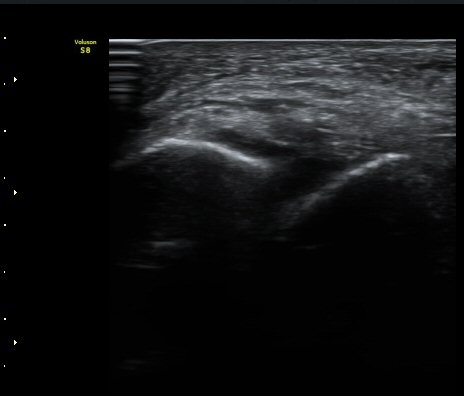

ÃÊÀ½ÆÄÅõ½ÃÇÏ ºÎÇϰ˻翡¼­ ºñ°ñ°ú ÀÎ´ë ºÎÂøºÎ¿Í ºñ°ñ°ú °Å°ñ »çÀ̰¡ ¹ú¾îÁø´Ù

(樨毢 1)

Àü°Å°ñºñ°ñÀÎ´ë ¼Õ»óÀÌ °üÂûµÇ´Â °æ¿ì ¹Ýµå½Ã ÃÊÀ½ÆÄÅõ½ÃÇÏ ºÎÇϰ˻縦 ½ÃÇàÇÏ¿©

ÀδëÀÇ ¿ÏÀü ÆÄ¿­·Î ºÒ¾ÈÁ¤¼ºÀ» º¸ÀÌ´Â °æ¿ì 3ÁÖ ÀÌ»ó ¼®°í°íÁ¤ÀÌ ¹Ù¶÷Á÷ÇÏ´Ù.